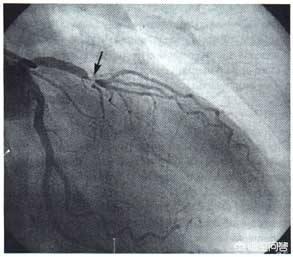

- Les produits de contraste "éclairent" les artères coronaires :Les artères coronaires du corps humain sont relativement petites : le tronc principal des artères coronaires ne mesure que cinq ou six millimètres, certaines des branches les plus importantes mesurent environ deux ou trois millimètres, et les autres sont des branches encore plus petites ; ces vaisseaux sanguins sont reliés aux tissus environnants et sont recouverts par les os, les muscles, etc. devant eux. Lors de la coronarographie, un agent de contraste est injecté à l'intérieur du cathéter mentionné plus haut afin de remplir les artères coronaires d'agent de contraste.L'agent de contraste est un médicament imperméable aux rayons X qui "illumine" les artères coronaires pendant la coronarographie afin que nous puissions voir clairement la distribution, la taille et la présence de sténoses et d'obstructions dans les artères coronaires.

- La DSA (Digital Subtraction Angiography) est une caméra pour les vaisseaux sanguins :L'équipement utilisé pour prendre des photos des artères coronaires mentionné plus haut est le DSA, qui est en fait également une forme d'examen aux rayons X, capable de prendre des photos et d'enregistrer des vidéos des différentes artères coronaires sous de multiples angles tout en injectant le produit de contraste, ce qui peut être considéré comme un angle de 360 degrés sans issue, et ces photos et vidéos peuvent être déposées sur un CD-ROM pour être facilement conservées et analysées.C'est parce que la coronarographie permet d'obtenir des photographies et des vidéos d'une telle clarté que la coronarographie est l'étalon-or du diagnostic de la maladie coronarienne.

La cardiographie, également connue sous le nom de coronarographie, est l'un des examens les plus courants pratiqués par les cardiologues et constitue l'examen de référence pour confirmer le diagnostic de maladie coronarienne ! Qu'est-ce qu'une cardiographie ? Un cardiogramme est réalisé par une approche artérielle, notamment par les artères radiales, fémorales et artérielles. L'approche artérielle est utilisée pour amener un cathéter jusqu'à l'ouverture de l'artère coronaire, à partir de laquelle un produit de contraste est injecté et l'artère coronaire est visualisée à la radiographie.